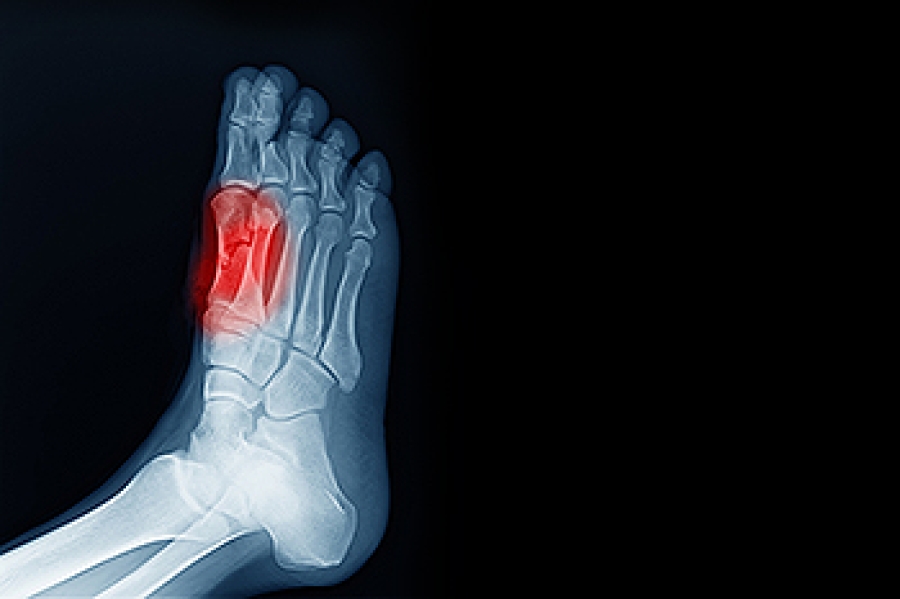

Can Sesamoiditis Heal On Its Own . Sesamoiditis refers to irritation and inflammation of the tendons surrounding the sesamoid bones. If symptoms don’t fade within a week. Symptoms can include pain, bruising, swelling, and more. follow your doctor’s instructions and your body's signals to allow your foot to heal properly and prevent. Conservative treatment options may include:. sesamoiditis is pain around the two small bones (the sesamoid bones) below the metatarsal head where it adjoins the big. fortunately, most sesamoid problems go away on their own without surgery, and when surgery is needed, it is successful at. resting and keeping pressure off the foot can allow the sesamoid and tendons to heal on their own. Some bouts of sesamoiditis may take longer to heal.

fortunately, most sesamoid problems go away on their own without surgery, and when surgery is needed, it is successful at. sesamoiditis is pain around the two small bones (the sesamoid bones) below the metatarsal head where it adjoins the big. Conservative treatment options may include:. Symptoms can include pain, bruising, swelling, and more. resting and keeping pressure off the foot can allow the sesamoid and tendons to heal on their own. Some bouts of sesamoiditis may take longer to heal. Sesamoiditis refers to irritation and inflammation of the tendons surrounding the sesamoid bones. If symptoms don’t fade within a week. follow your doctor’s instructions and your body's signals to allow your foot to heal properly and prevent.